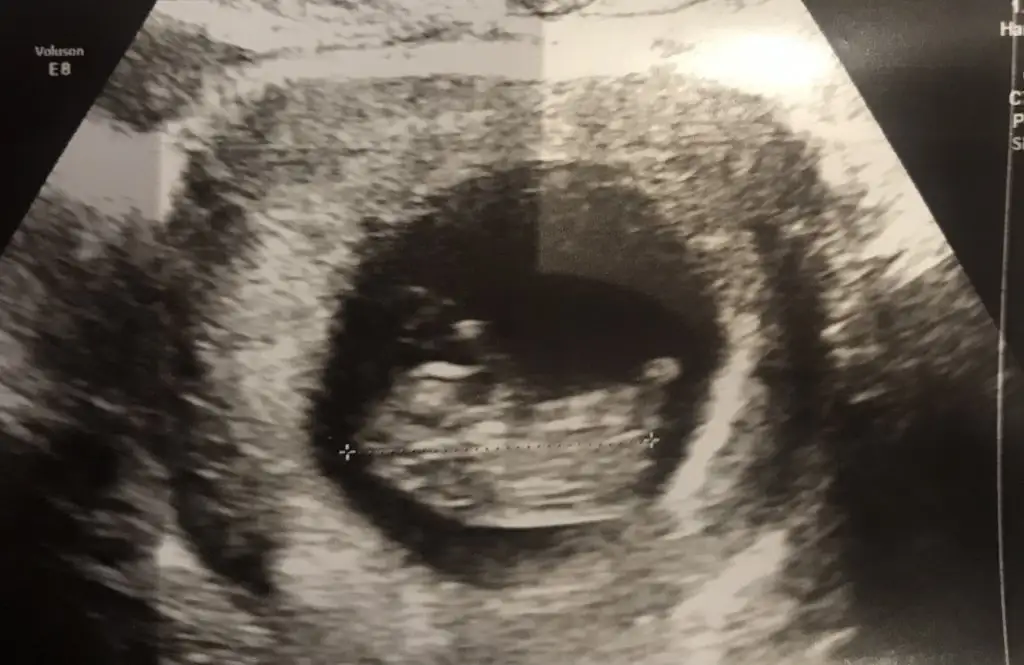

ErkekIkra meyra 13. Hafta bacak arasii yorumlar misinn

Çok teşekkür ederim yorum için çok sevgiler.Kız gibi